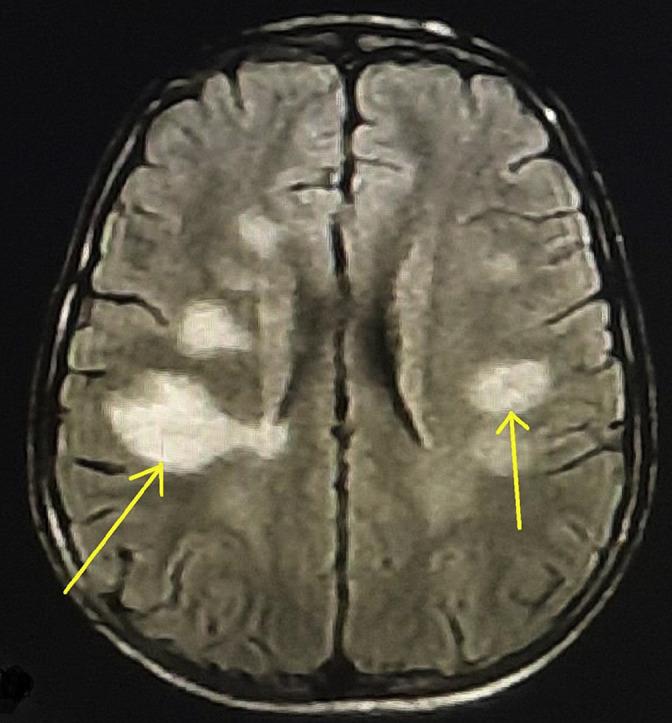

Movement disorders are extremely rare in acute disseminated encephalomyelitis (ADEM) and in the novel severe acute respiratory syndrome coronavirus (SARS-CoV-2) infection. We herein report a 34-years-old previously healthy woman who presented with a febrile illness and a constellation of movement disorders (predominantly myoclonus) followed by encephalopathy. After exclusion of common infectious, autoimmune and paraneoplastic etiologies, she was diagnosed to have COVID-19 induced ADEM, which responded to intravenous methylprednisolone and intravenous immunoglobulin. Our case adds to the tally of cases of post-SARS-CoV-2 infection related movement disorders and to the exceedingly rare list of cases in which movement disorders preceded ADEM.

运动障碍在急性播散性脑脊髓炎(ADEM)和新型严重急性呼吸综合征冠状病毒(SARS-CoV-2)感染中极为罕见。我们在此报告一名34岁既往健康的女性,她出现发热性疾病,并伴有一系列运动障碍(主要是肌阵挛),随后出现脑病。在排除常见的感染、自身免疫和副肿瘤病因后,她被诊断为COVID-19诱发的ADEM,对静脉注射甲泼尼龙和静脉注射免疫球蛋白有反应。我们的病例增加了SARS-CoV-2感染后相关运动障碍的病例数,也增加了运动障碍先于ADEM出现的极为罕见的病例清单。